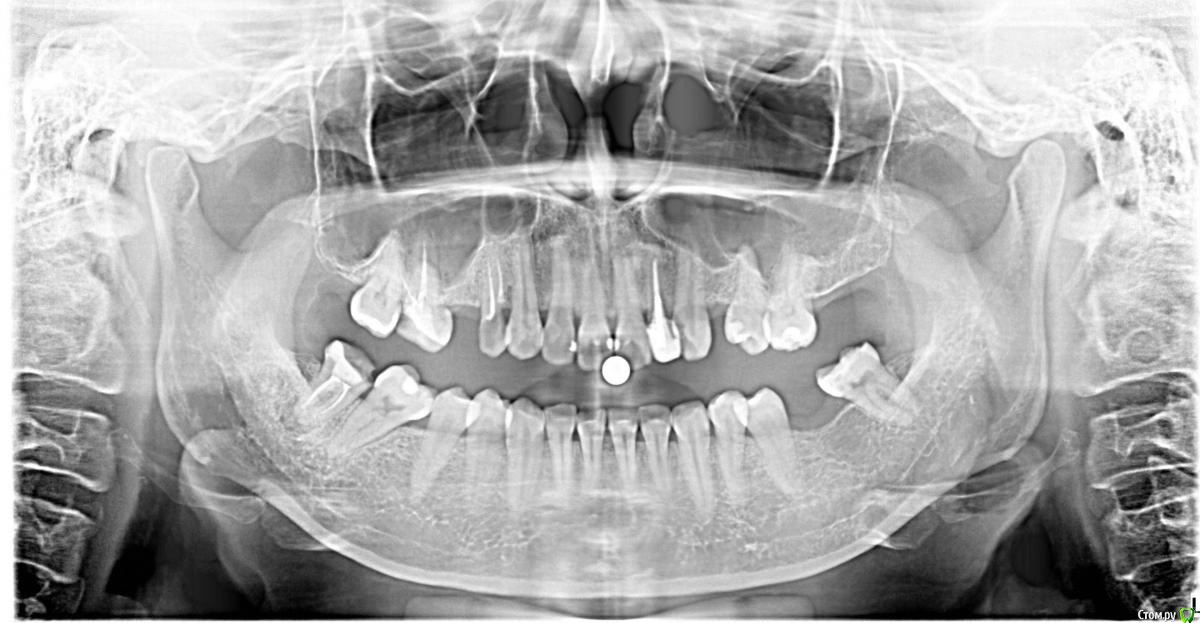

unvisage Опубликовано 29 сентября, 2017 Поделиться Опубликовано 29 сентября, 2017 посоветуйте, пожалуйста, что делать с зубами? Ссылка на комментарий

IvanK Опубликовано 2 октября, 2017 Поделиться Опубликовано 2 октября, 2017 А Вы сами чего хотите? Необходимо рациональное протезирование , обратитесь к ортопеду Ссылка на комментарий